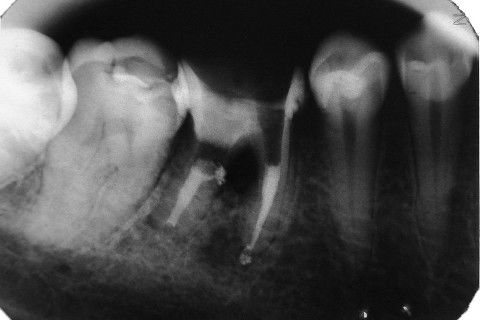

Retratamento de Canal, Tratamento de Perfuração, Restauração Provisória com Resina, Núcleo e Provisório.

RETRATAMENTO DE CANAL, TRATAMENTO DE PERFURAÇÃO, RESTAURAÇÃO PROVISÓRIA COM RESINA, NUCLEO E PROVISÓRIO.